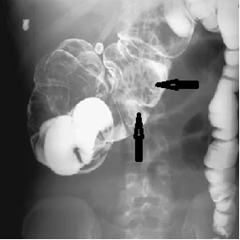

Radiology images of colocolic intussusception (arrows). The lead point was an endometrioma, a highly unusual source for an intussusception.